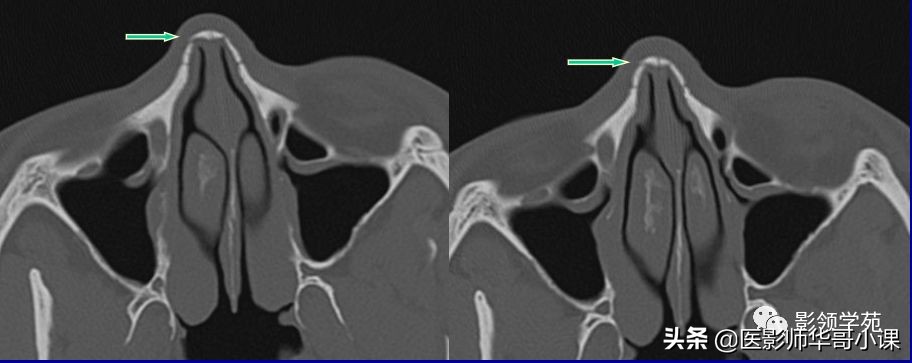

线性骨折 粉碎骨折

右侧鼻骨线形骨折

鼻骨线形骨折

左侧鼻骨线形骨折